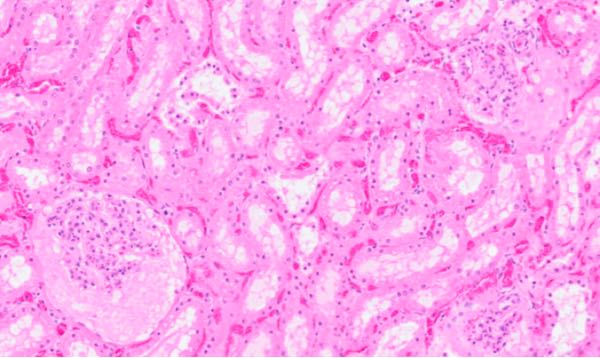

Heart histology (Image 6) of the ram lamb indicated marked, acute, multifocal to coalescing, monophasic myonecrosis with acute, diffuse myocardial degeneration and early repair. This change varied in severity with milder changes occurring in ewes that died earlier in the investigation, and more dramatic cardiac lesions with early repair in animals that took several days to die. Histologic changes of the liver and kidney of all animals examined were also present. Glomerular shrinkage with severe protein loss and tubular degeneration (Image 7) was observed in the kidneys. Liver sections revealed acute, diffuse, mild-to-moderate hepatic degeneration. Moderate, acute, multifocal pulmonary oedema was present in one ewe. Changes visible in the kidney, liver, and lung were attributed to hypoxic damage associated with circulatory failure due to the cardiac disease. Myoglobinaemia may have contributed to the renal lesions.